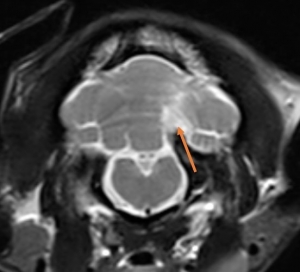

✎ 圖三為15歲馬爾濟斯狗狗出現頸部彎折和歪頭的症狀,檢查結果為小腦中風。

- MRI 是診斷黃金工具:能清楚觀察缺血/出血位置與範圍,一些特殊序列如加權梯度回波序列(T2*W、GRE)、擴散加權成像(DWI)等對出血及缺血性病灶極具診斷力